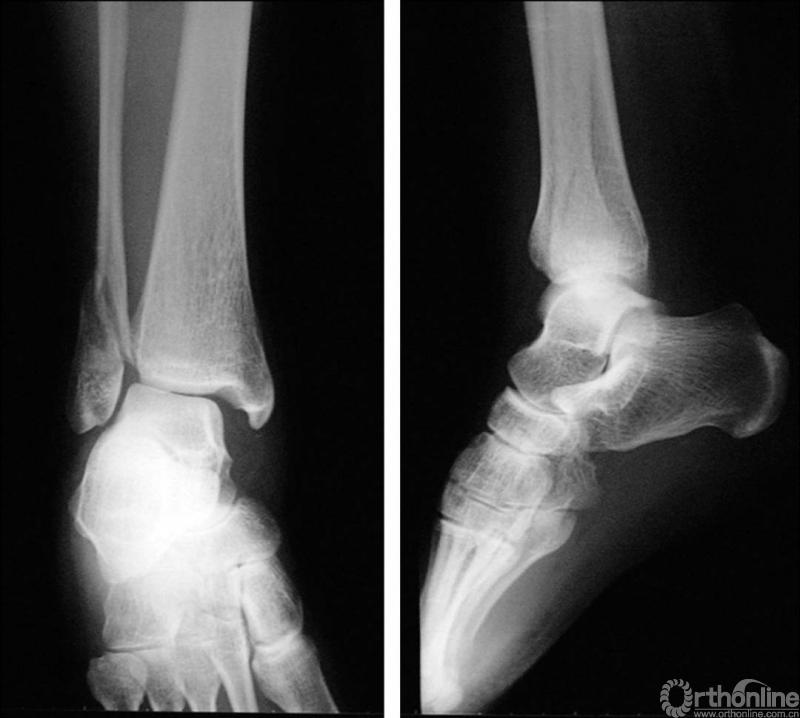

X线诊断:标准的踝关节影像学评估应包括3个位相:前后位(图5),踝穴位(内旋15°)(图6),侧位(图7)。

图5 前后位

图6 踝穴位(内旋15°)

当踝关节严重损伤时内外踝及距骨将发生不同程度的移位(图8)。有时外踝骨折会伴有三角韧带的损伤,静态的X线摄片并不能准确地反映踝关节的稳定性,应力位片及MRI检查可完善对踝关节稳定性及韧带损伤的评估(图9)。此时应通过患肢损伤机制及放射资料准确判断踝关节损伤的类型以正确指导复位和固定。有时单纯内踝骨折可能是更为复杂的“Maisonneuve骨折”的一部分,该骨折还包括腓骨近端骨折及韧带联合损伤,故X线检查应投照整个胫腓骨。

图8 骨折移位明显合并有脱位